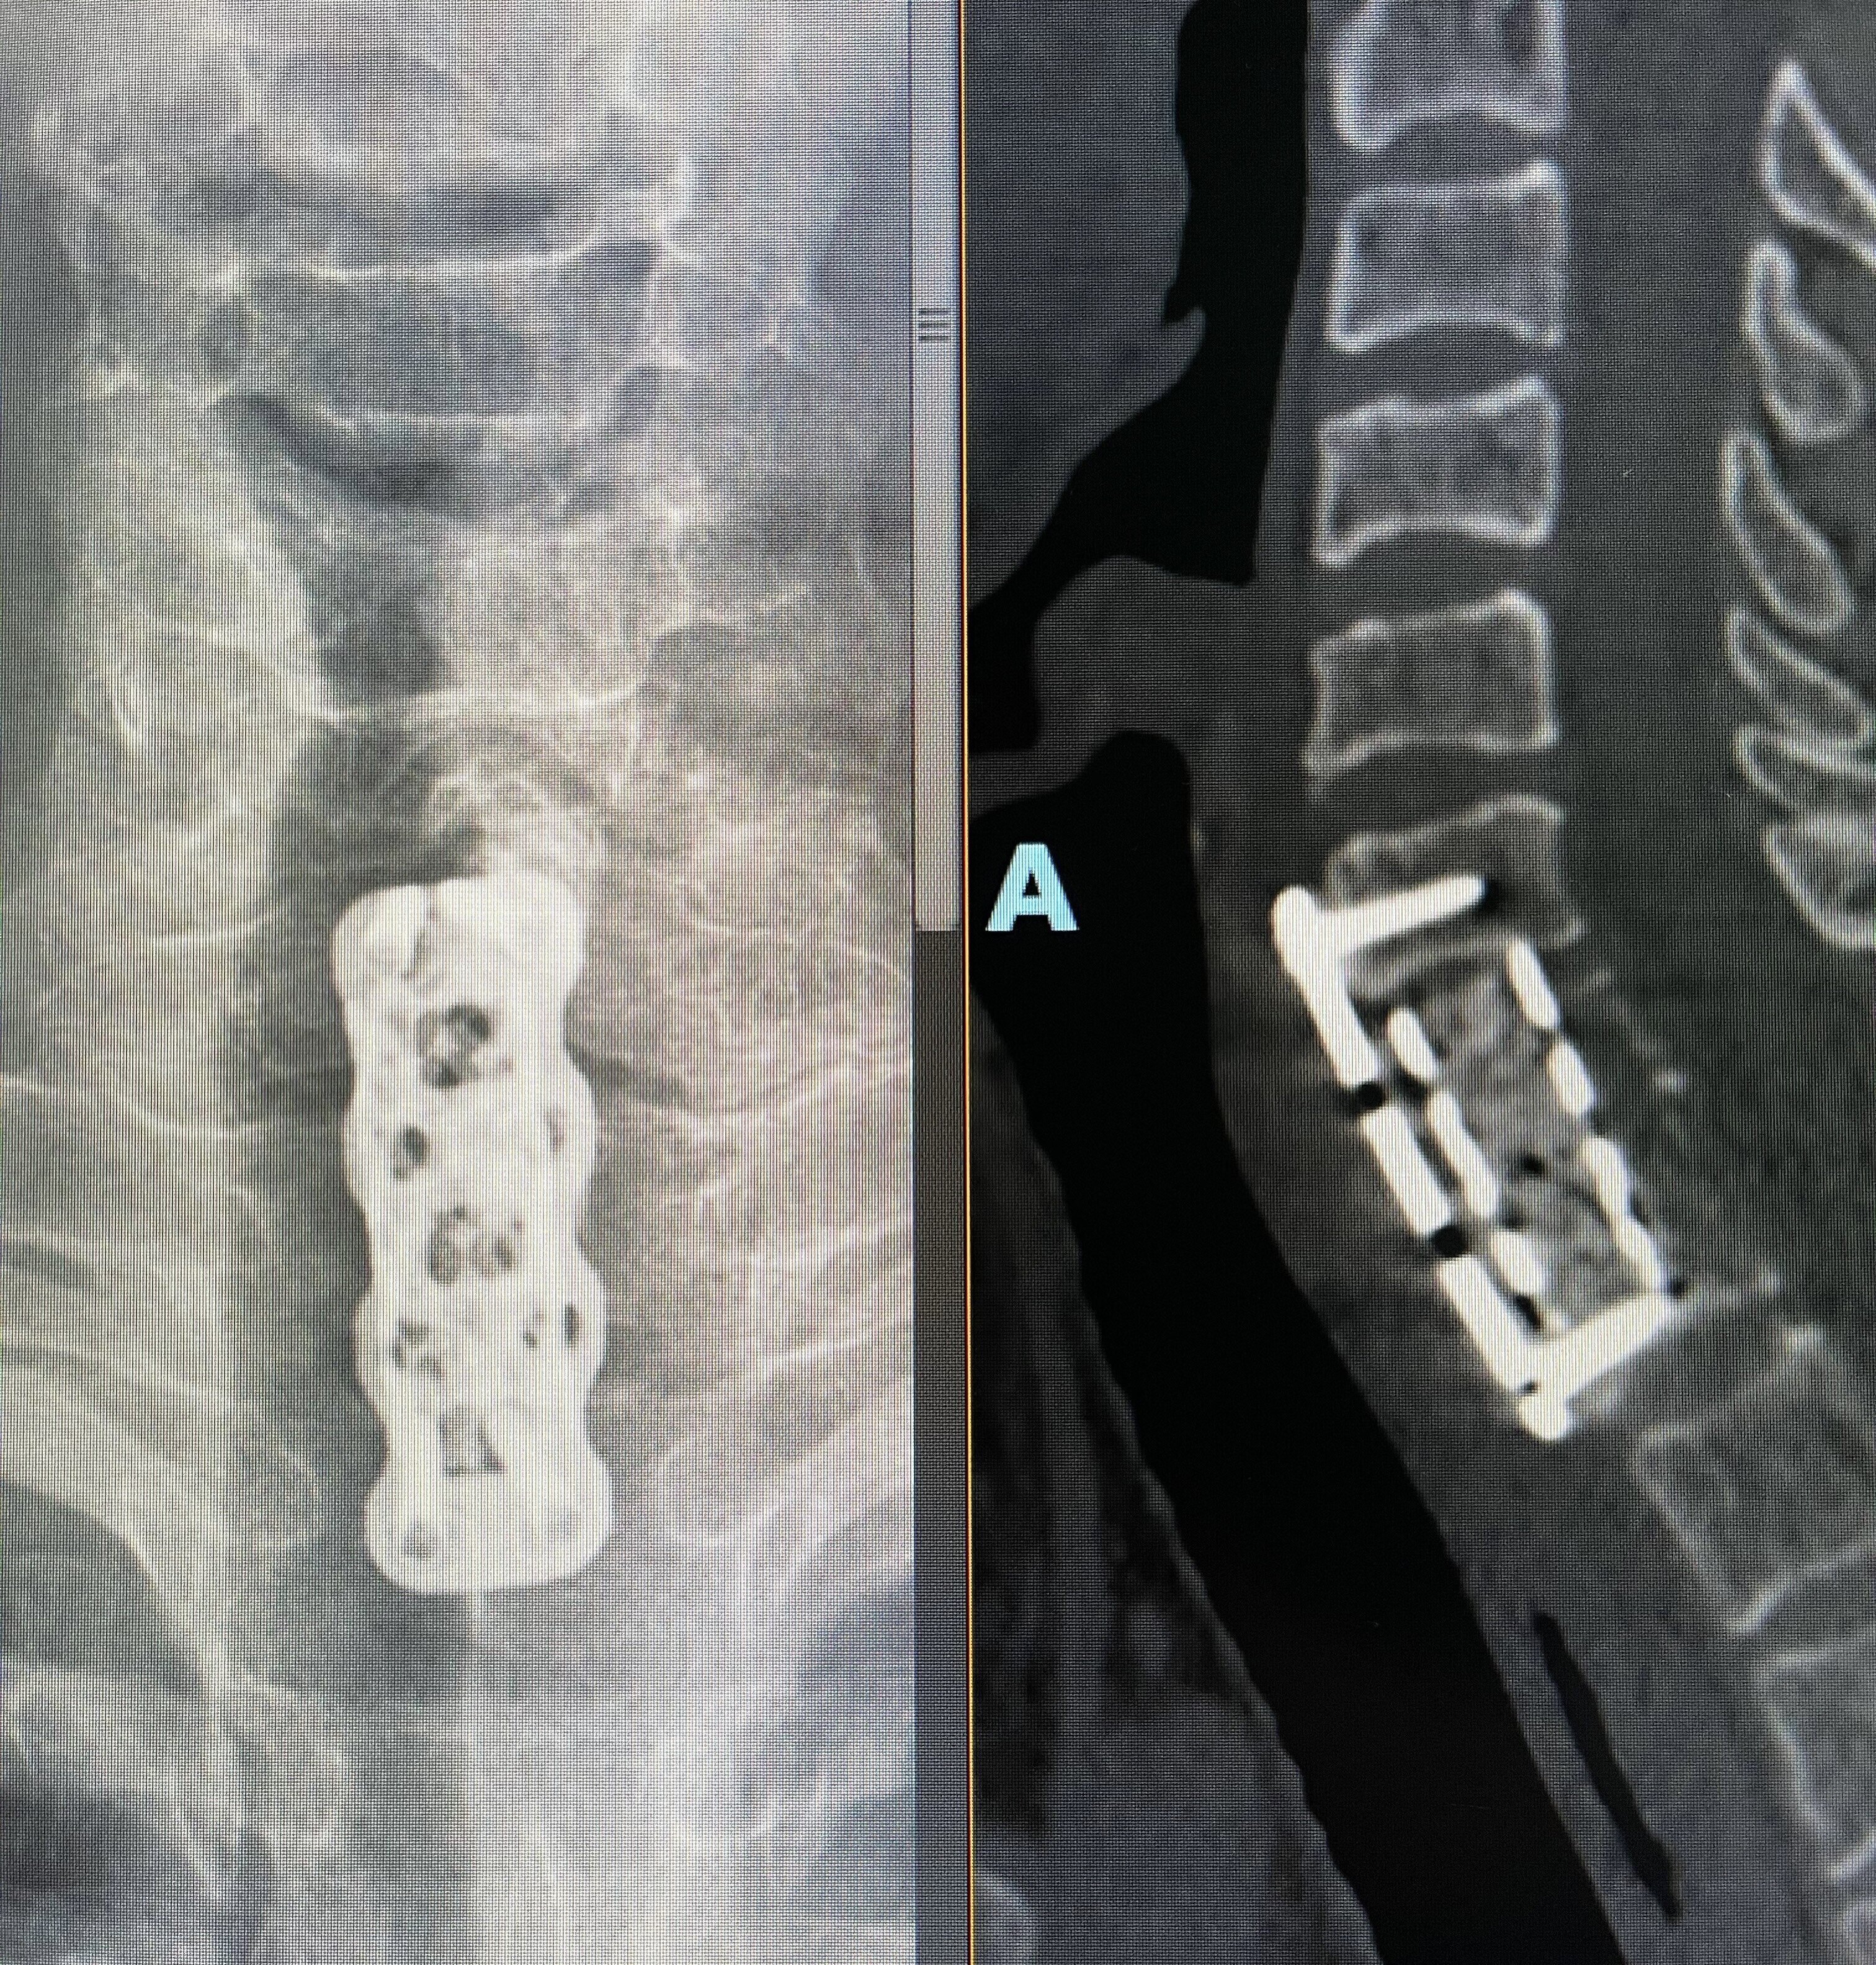

2.病理性骨折 所谓病理性骨折就是指在没有收到暴力打击,仅在轻微外力、甚至是“打喷嚏”、弯腰动作出现的中轴骨(脊柱、肋骨、骨盆)和四肢骨折。其原因就是肿瘤细胞侵蚀、破坏了骨的正常结构、硬度和强度下降,导致轻微的外力作用下就出现骨折。

3.肿块 往往在骨破坏的区域会出现周围软组织受累及、局部软组织肿块形成,常常伴有疼痛、压痛的症状和体征!

4.神经受压症状 最常见的脊柱转移瘤在骨破坏的同时,局部软组织肿块形成压迫脊髓或神经根;以及椎体的病理性骨折瘤骨突入椎管和神经根管,出现脊髓和神经根受压症状,严重时出现瘫痪(下肢无力、麻木,大小便障碍等)症状!

出现这几种常见的情形后,一、做好及时就医,前往专科就诊。二、相信骨转移仍然可治(a.药物治疗:骨保护药物;b.放射治疗:止痛、抗肿瘤;c手术干预:经皮穿刺椎体球囊扩张成形术、骨成形术等微创手术,病理性骨折开放手术,脊柱转移瘤的分离手术?立体定向放疗技术结合等)。三、相信合理的规范治疗,骨转移瘤仍然可以达到带瘤生存,部分单发转移积极治疗后,甚至可达到无瘤生存。四、由此,保持良好的心态,积极阳光的接受治疗同样对康复很关键。